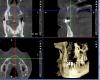

samsonov Опубликовано 27 июня, 2013 Поделиться Опубликовано 27 июня, 2013 Сегодня дали КТ.Как думаете,идти по варианту "цистотомия",либо удастся заполнить сразу полость? Ссылка на комментарий

IvanK Опубликовано 27 июня, 2013 Поделиться Опубликовано 27 июня, 2013 Я бы попробовал сразу заполнить 10 дней назад была пациентка, ячейка пазухи, полностью изолирована от основной пазухи, на КТ вид как у Вас, только размер чуть меньше. Удалял зуб, случилось сообщение с ячейкой. Все почистил, помыл, серабон. Сегодня снял швы, полет нормальный. Что-то типа крестального синус-лифтинга Ссылка на комментарий

kriokov Опубликовано 27 июня, 2013 Поделиться Опубликовано 27 июня, 2013 так бы сделалразрез по прикрепленной , далее вертикально поглубже, окно вестибулярно, небно вообще бы мягкие ткани не трогал ,далее цистэктомия, перфо в нос может и не быть , графт бы пихать не стал, (много надо, и риск что нагноиться), и ушился бы без натяга.цистотомия не лучший вариант, получите костный дефект здоровый.при эктомии - получаете почти замкнутый , сгусток свое дело потом сделает. Еще - не стал бы "скрести" полость, наоборот отработал бы кюретой от кости. 1 Ссылка на комментарий

sergio Опубликовано 28 июня, 2013 Поделиться Опубликовано 28 июня, 2013 Костная стенка очень тонкая,имхо,не получится полноценно вылущить оболочку,не проткнув стенку.лучше сначала цистотомию провести.по поводу графта:без него такой костный дефект,скорее всего,просто зарубцуется,поскольку кровяной сгусток сократиться уже после ушивания Ссылка на комментарий

kriokov Опубликовано 28 июня, 2013 Поделиться Опубликовано 28 июня, 2013 (изменено) Костная стенка очень тонкая,имхо,не получится полноценно вылущить оболочку,не проткнув стенку.лучше сначала цистотомию провести.по поводу графта:без него такой костный дефект,скорее всего,просто зарубцуется,поскольку кровяной сгусток сократиться уже после ушиваниядавайте попробуем + и - обсудитьцистотомия-плюсы- если в нос сильно вылезишь, не критиноминусы- получаем 100% дефект, долгое заживление, если потом имплантация , то серьезные заморочки с аугментациейцистэктомияплюсы- при нормальном исходе, дефект после заживления будет вестибулярно, но минимальный, заживет быстрее, чем при томиисохраним дефект условно замкнутым, будут условия для нормальной стабилизации сгустка с оставшейся костьюминусыаккуратность выполнения манипуляцийриск нагноения- решаемо, но заживать дольше будет и дефект соответственно большериск дыры в нос- решаемо, смотря какая по ситуации. Но лучше без нее.Про графт не знаю, так как в таких дефектах при кистах не применял.примерно такая же ситуация, только еще два зуба на выносСутки после цистэктомии удаления двух резцовпо моему 4 мес после эктомиии снимок локальный этой зоны чуть позже, кт не делал, протезировали не у насПо ходу операции- штатно, в нос не вышел, из резцового кровило но не очень, резцы слева удаленыОбратился с нагноением, сначала декомпрессия и неделю отмывался, через 6 недель по здоровым мягким тканям цистэктомия Изменено 28 июня, 2013 пользователем kriokov 2 Ссылка на комментарий

Alexey Doc Опубликовано 29 июня, 2013 Поделиться Опубликовано 29 июня, 2013 (изменено) Мне кажется в этом случае разумнее будет вначале путем создания декомпресии, уменьшить объем костной полости а уже затем проводить цистэктомию! Согласен что при классической цистотомии получим большой дефект. Изменено 29 июня, 2013 пользователем Alexey Doc Ссылка на комментарий

АнтонТЛТ Опубликовано 29 июня, 2013 Поделиться Опубликовано 29 июня, 2013 Здесь все-таки представлен кейс не совсем рутинный.А чем он не рутинный? Только размер большой и всё. Там похоже, что есть кость между кистой и носом. 2 Ссылка на комментарий

OMFS Опубликовано 2 июля, 2013 Поделиться Опубликовано 2 июля, 2013 Я за цистэктомию.Может попробовать зайти с небной стороны, там такой контур все равно не нужен.Сделать доступ, уберется максимально выступающая часть, вылущить оболочку, графт и мембрану. Ссылка на комментарий